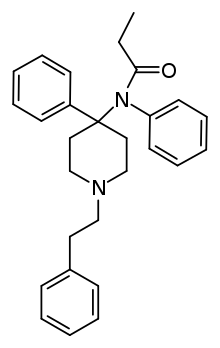

Anilidopiperidines

- 3-Allylfentanyl

- 3-Methylfentanyl

- 3-Methylthiofentanyl

- 4-Phenylfentanyl

- Alfentanil

- α-Methylacetylfentanyl

- α-Methylfentanyl

- α-Methylthiofentanyl

- Benzylfentanyl

- β-hydroxyfentanyl

- β-hydroxythiofentanyl

- β-Methylfentanyl

- Brifentanil

- Butyrfentanyl

- Carfentanil

- Fentanyl

- Lofentanil

- N-Methylcarfentanil

- Mirfentanil

- Ocfentanil

- Ohmefentanyl

- Parafluorofentanyl

- Phenaridine

- R-30490

- Remifentanil

- Sufentanil

- Thenylfentanyl

- Thiofentanyl

- Trefentanil

Structures